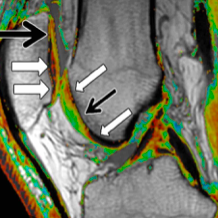

Qual é o principal achado na RNM da condromalácea patelar?

Edema ósseo e lesões na cartilagem patelar.